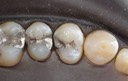

Joe Cha #18 finish

Wayne Chin #5 pre-op